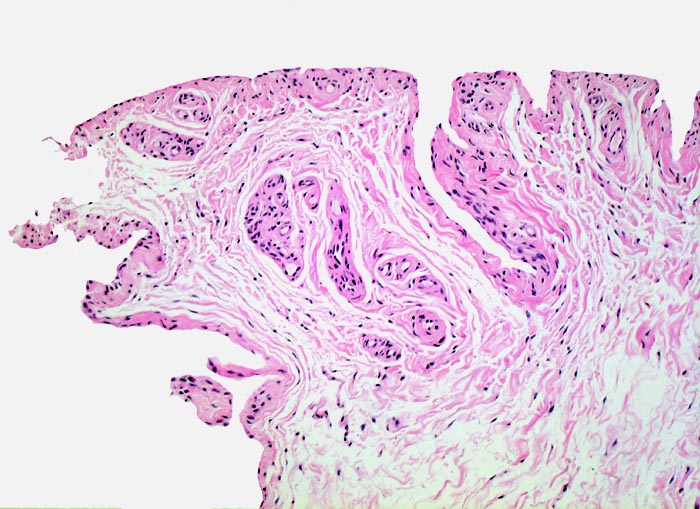

normale Synovialis

Synovialis

Die Innenauskleidung von Gelenken, Sehnenscheiden und Bursen wird von einer spezialisierten epithelähnlichen Synovialmembran ausgekleidet. Diese sezerniert Synovia. Die Synovialis besteht aus 1-4 Synovialzellagen, die an der Unterseite mit einer Zone von lockerem gut vaskularisiertem kollagenem Bindegewebe verschmelzen, in dem Fettzellen, Fibroblasten, Mastzellen und Makrophagen vorkommen. Eine kontinuierliche Basalmembran ist nicht ausgebildet. Die Synovialzellen können flach und mesothelähnlich, spindelförmig, polyedrisch oder kubisch sein. Typ A Synoviozyten sind phagozytisch tätig, Typ B Zellen produzieren reichlich Proteine und haben entsprechend ein gut entwickeltes rauhes endoplasmatisches Reticulum.

Synovialis von Fingergelenk

100